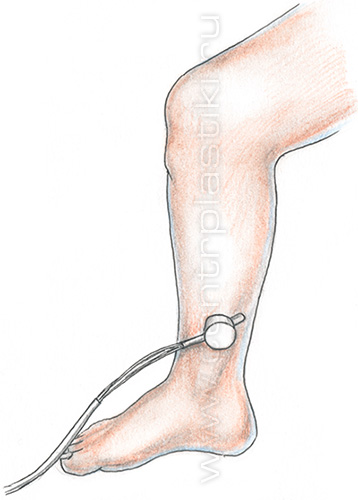

Фотоплетизмография.

Плетизмография основана на принципе изменения объема на измеряемом участке, происходящего из-за динамического колебания количества крови (любой орган состоит из тканей и количества заполняющей его крови). Поскольку объем тканей во время исследования является постоянной величиной, а объем крови в органе постоянно изменяется, то динамика этого процесса может быть измерена специальным прибором – плетизмографом, в состав которого входят плетизморецептор, трансформирующий или усиливающий модуль и регистрирующая аппаратура.

Фотоплетизмография – это метод, регистрирующий оптическую плотность исследуемой ткани или органа.

Нужный участок ткани просвечивают инфракрасным светом, который затем попадает на фотопреобразователь. Чем интенсивнее был отраженный или рассеянный свет, тем больше в исследуемом участке (органе) было крови.

Также этот метод способен учитывать изменения света, отражающегося от кожи. Так как проникающая способность источника света составляет всего от 0,3 до 2,25 мм, таким образом исследуют субпапиллярные венулярные сплетения.

Поскольку изменение возвратного кровотока влияет на заполнение и опорожнение в подкожном венулярном сплетении, то можно зарегистрировать эти изменения и сделать соответствующие выводы.

Метод неэффективен при наличии каких-либо сопутствующих заболеваний артерий, сердечной недостаточности, остром местном воспалении, заболеваниях суставов, местных дистрофических изменениях мягких тканей.